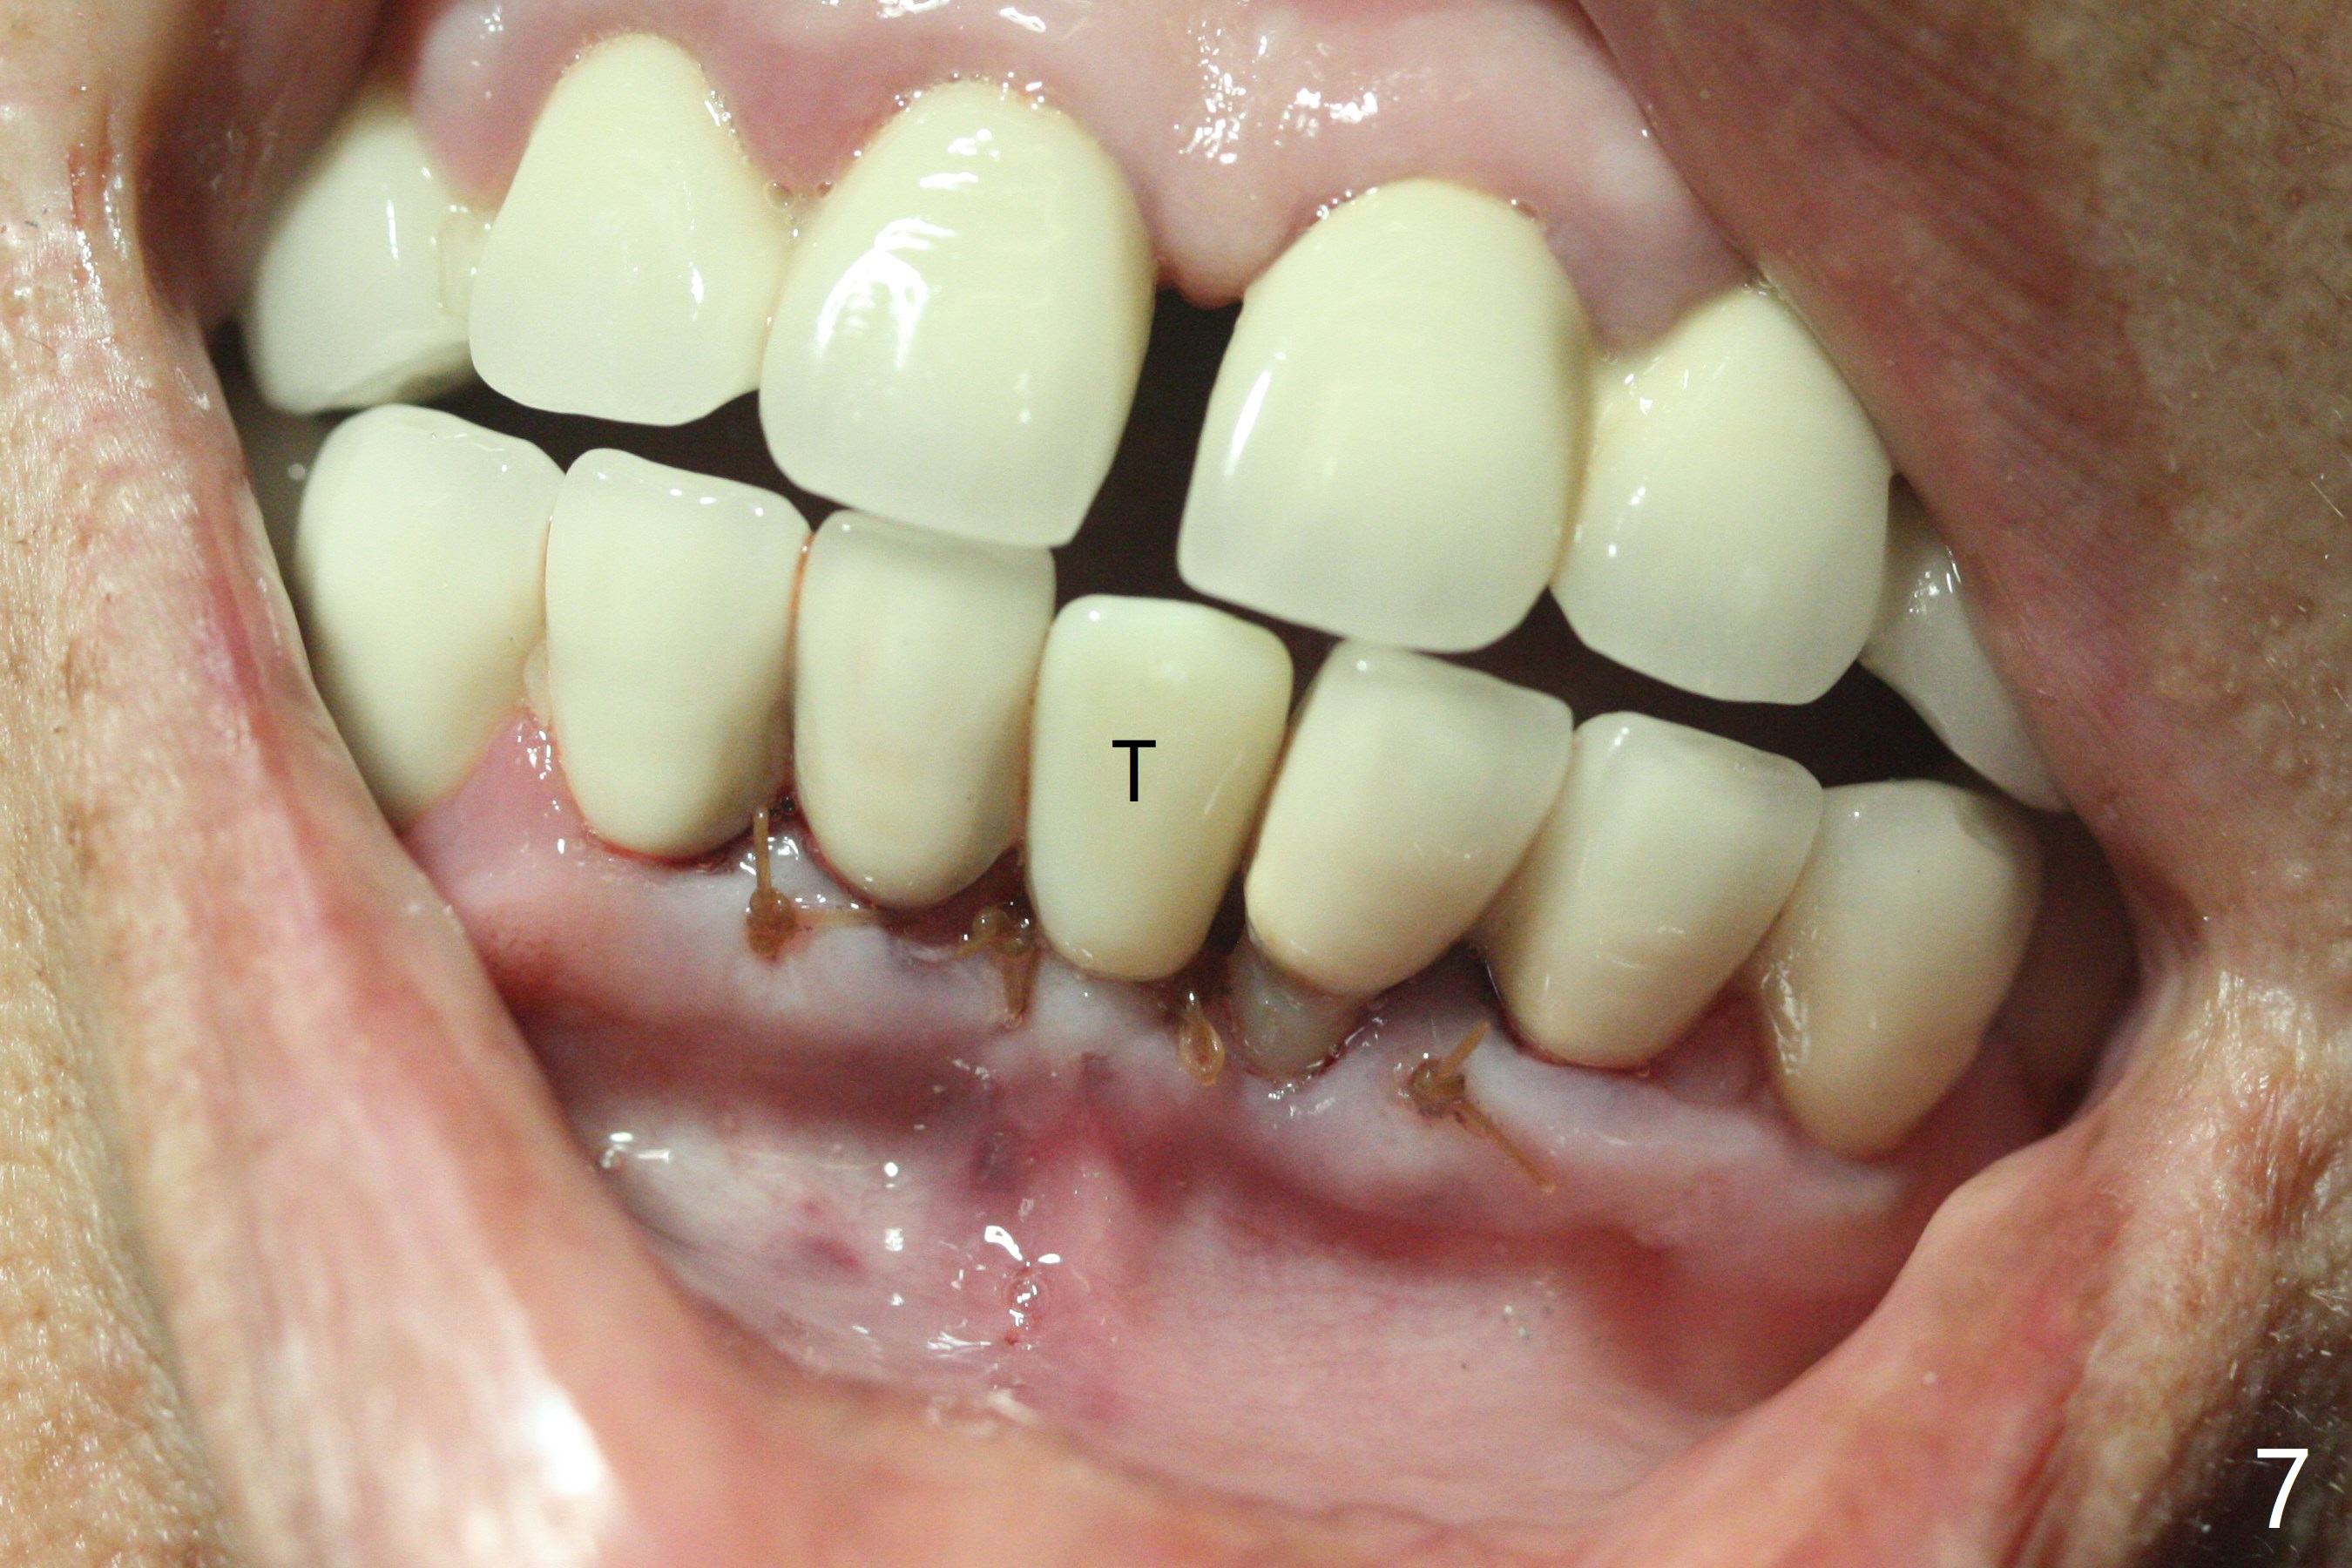

种植前与66岁女病人再次讨论下前牙正中种植可能产生不对称问题,她好像不在乎。术前检查显示下前牙正中间隙偏左(图一),处理似乎容易,但是牙槽嵴相当狭窄(图一 *,二 箭头)。牙槽嵴切除后(大约3 毫米宽(颊舌侧)),初期钻洞似乎偏移右边(图三),矫正后(图四),植入2乘10(4)毫米连体植体(图五,比预计小,因为骨质薄),放置骨粉(图五,六 *)和膜,缝合,制作即刻修复物(图七 T),病人满意,牙槽骨饱满了。术后一个多月临时牙冠取出修正,伤口愈合,由于植骨颊侧没有凹陷(图八),而舌侧隆起(图九:*,与图二术前对比)。其实病人不小心吃牛肉时损伤植体,疼痛几天。尽管最近吃饭时植牙又受伤,但是没有松动,也没有骨质吸收,就是局部结石多(图十,术后四个月)。正式牙冠术后4.5个月粘固(图十一)。